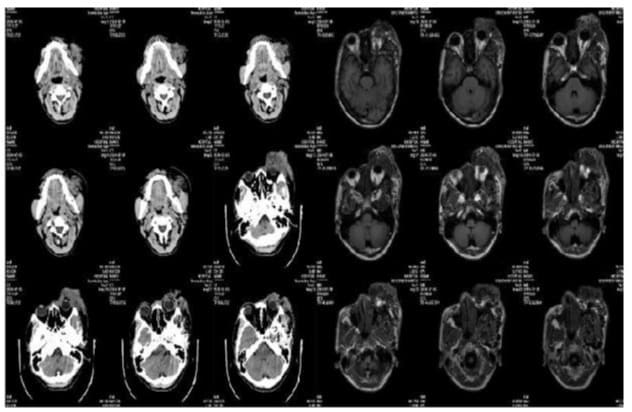

The CT and MR scans revealed the presence of several abnormal blood vessel formations in various areas including the nose, left eye area, upper jaw and face, temporal region, lower temporal region, space behind the throat, and space around the salivary gland. These formations surround the left eyeball and affect the left eye socket, cheekbone, and sphenoid bone (Figure 2). The patient has bilateral cavernous sinus and left supraocular vein reflux, along with the presence of coils in several locations. Additionally, there is an aberrant thickening of the trunk and branches of the left internal carotid artery, as seen in (Figure 3).

Figure 2: The left side is the CT of the patient, and the right side is MR image: the nasal, left periorbital, maxillofacial area, part, temporal fossa, inferior temporal fossa, parapharyngeal space, and parotid gland space showed multiple tortuous tubular vascular shadows, and the enhanced scan showed vascular-like enhancement, and the tortuous perivascular and vascular space showed flaky soft tissue shadows, the boundary was unclear, and the overall large layer of the lesion was about 83x52x42 mm (not fully encapsulated), and the lesion surrounded the left eyeball, involving the left orbit, zygomatic bone, and sphenoid wing.

Figure 3: DSA on admission for the first time: the left orbit and the surrounding huge contrast agent concentration area can be seen, the blood vessels are very abundant, mainly supplied by multiple branch blood vessels of the left external carotid artery, and a small part is supplied by the left ophthalmic artery, the flow is very large, and the flow is very large, and the return to the bilateral cavernous sinus and the left superior ocular vein, spring coils can be seen in many places, and the main trunk and branches of the left internal carotid artery are abnormally thickened.